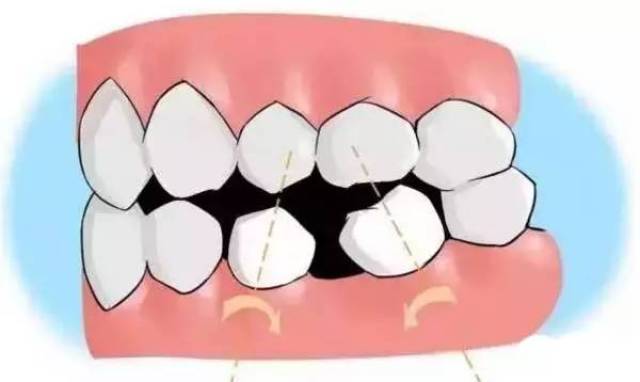

- 相邻的健康好牙会失去支撑,向缺牙空隙倾斜,移位,松动,相邻牙齿也

- 6,牙齿倾斜或牙齿长期缺损,导致相邻牙齿移位.

- 缺牙空隙内倾斜,移位,缺牙空隙相对应的牙齿将因无力量而逐渐伸长

- (会导致响铃牙齿倾斜或对咬牙增长)

- 缺失牙临近的牙齿向缺隙处倾斜

- 缺牙空隙内倾斜,移位,缺牙空隙相对应的牙齿将因无力量而逐渐伸长